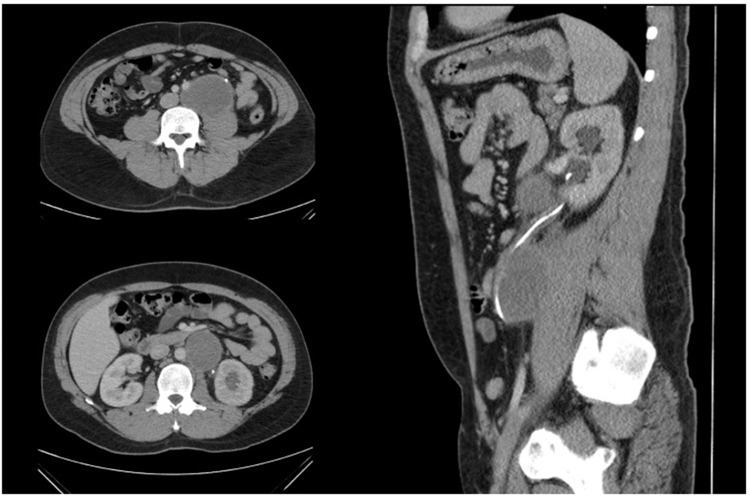

背景:腹膜后淋巴结清扫术(RPLND)在转移性睾丸癌的治疗管理中起着不可或缺的作用。作为一项大手术,RPLND有明显并发症的风险,特别是在化疗后(PC-RPLND)的情况下。我们评估了在澳大利亚一家三级医院引入RPLND作为一项新服务的安全性。方法:实施严格的方案,优先考虑适当的病例选择,多学科的外科专业知识和随时进入重症监护设施,以引入RPLND。前瞻性数据收集于2020年10月至2022年10月在墨尔本北部医院接受PC-RPLND的患者。主要终点和次要终点分别为术后30天Clavien-Dindo (CD)分级、并发症发生率和围手术期质量指标。结果:6例患者行双侧开模板PC-RPLND,平均年龄28.7±4.3岁。中位淋巴结计数为17 (IQR = 16),组织病理学检查均发现转移性生殖细胞瘤。中位住院时间为6天(IQR = 3),其中重症监护1天。不需要输血,也没有遇到30天的CD并发症。中位随访22个月(IQR = 21),无复发或明显的延迟并发症。结论:在严格的协议下,RPLND作为一项新服务安全地引入了我们的高等教育机构。围手术期质量终点与高容量国际中心相匹配。

Results: Six patients (mean age 28.7 ± 4.3 years) underwent bilateral template open PC-RPLND. Median node count was 17 (IQR = 16) with metastatic germ cell tumour identified in all patients on histopathology. Median length of stay was 6 days (IQR = 3) with 1 day in intensive care. No blood transfusions were required, and no 30-day CD complications were encountered. Median follow-up was 22 months (IQR = 21) with no recurrences or significant delayed complications.